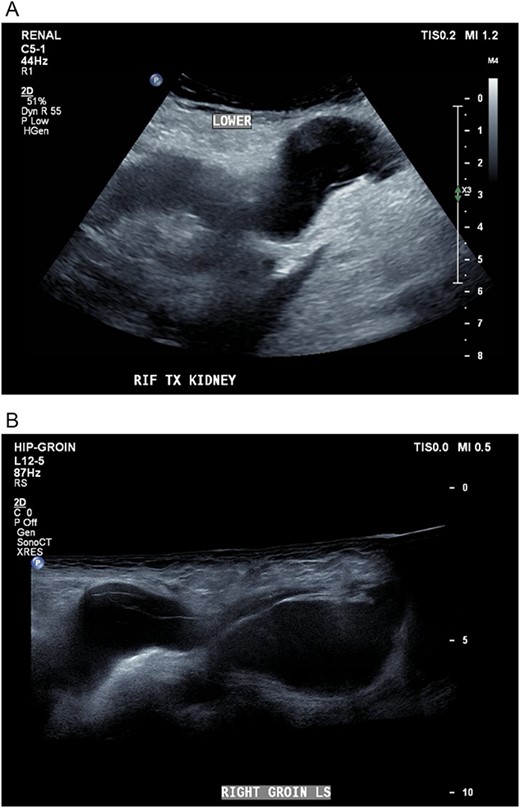

Five days later, the patient had another ultrasound and an ensuing CT KUB given recurrence of a painful groin swelling overnight. It showed a reaccumulation of the pelvic fluid collection, which extended into the groin toward the scrotum with two pockets of fluid collection measuring 4.6 × 6.5 × 2.7 cm (42 ml) and 7.7 × 3.5 × 4.6 cm (66 ml) (Figs 2 and 3). We temporized the situation by aspirating 35 ml of fluid by the bedside under ultrasound guidance for symptom relief and booked him for an elective operation given the complex anatomy of the collection.

(A, B) Targeted ultrasound showing reaccumulation of a peri-transplant collection which appeared multiloculated measuring a total of 100 ml extending into the right groin.

Coronal CT scan showing lobulated low-density fluid collection adjacent to the lower pole of the transplant kidney in the right iliac fossa and extending into the superficial inguinal canal tracking along the inguinal and scrotal hernia with a maximal width of 43 mm in transverse diameter.